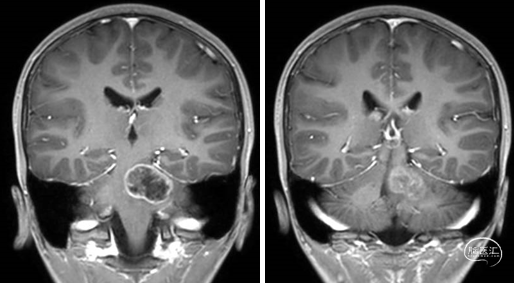

2023年9月13日 MRI T2

2023年9月13日 MRI+C